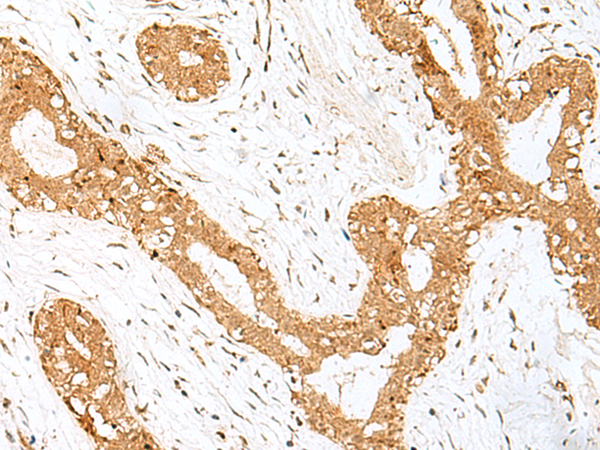

IHC positive control: |

Human thyroid cancer |

IHC Recommend dilution: |

40-200 |